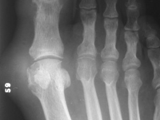

Gout-foot

Gout-foot